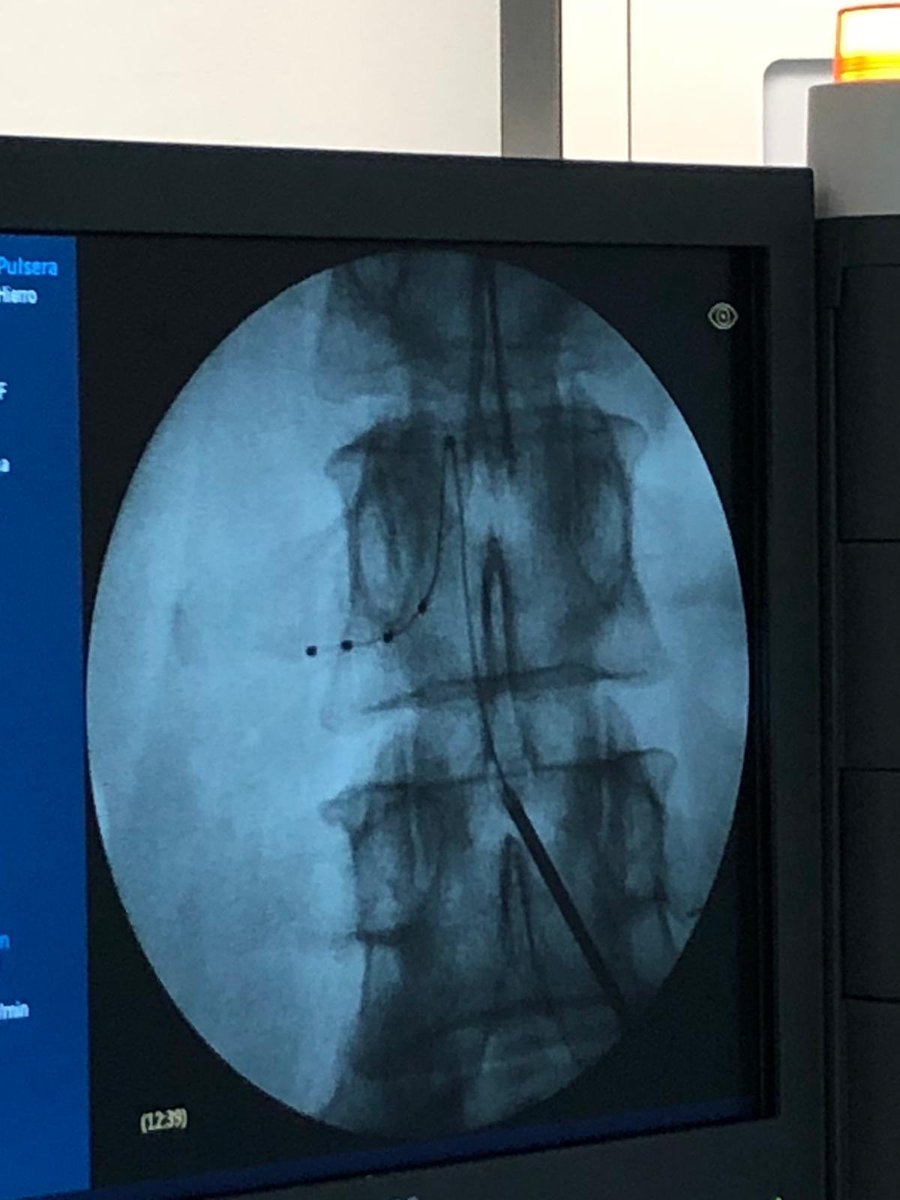

The art of DRG stimulator implant. Best team ever @agustinmendioladela

#spinalcordstimulation#chronicpain#painrelief#drgstimulator@AbbottGlobalpic.twitter.com/HKajnX5aSr